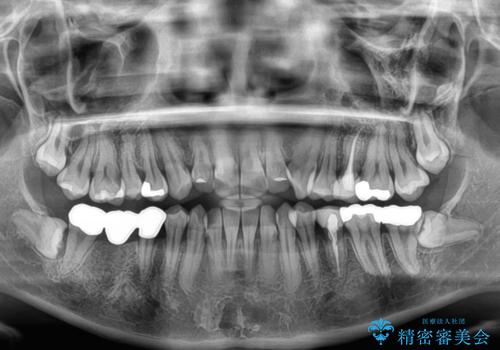

- 上下前歯のデコボコとクロスバイトを気にして来院された患者様です。

治療済みの処置歯が多いため、インビザラインを用いて矯正治療を行うこととしました。

下顎臼歯部にブリッジが装着されており、移動不可のため、IPR(歯と歯の間を削る)と歯列全体を拡大させることで、歯並びを整えていくこととしました。